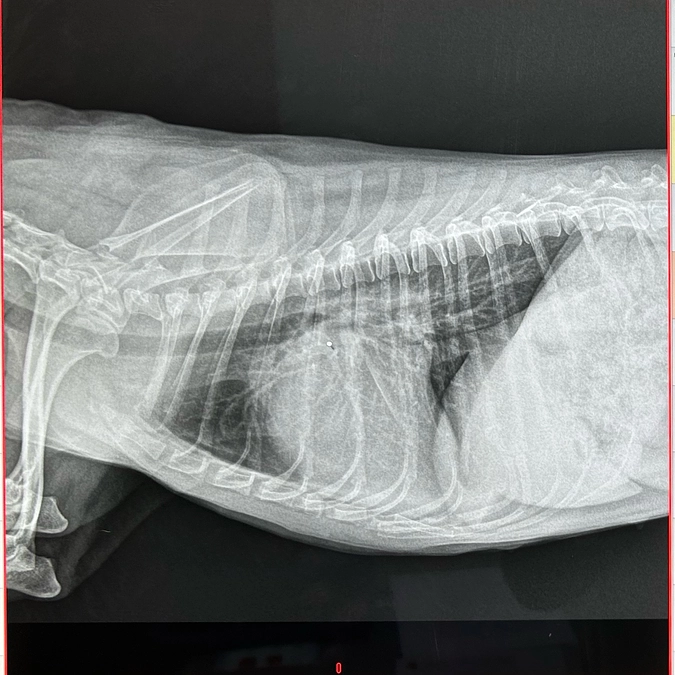

いつも病院ではエコー、レントゲン、血液検査を受けます。